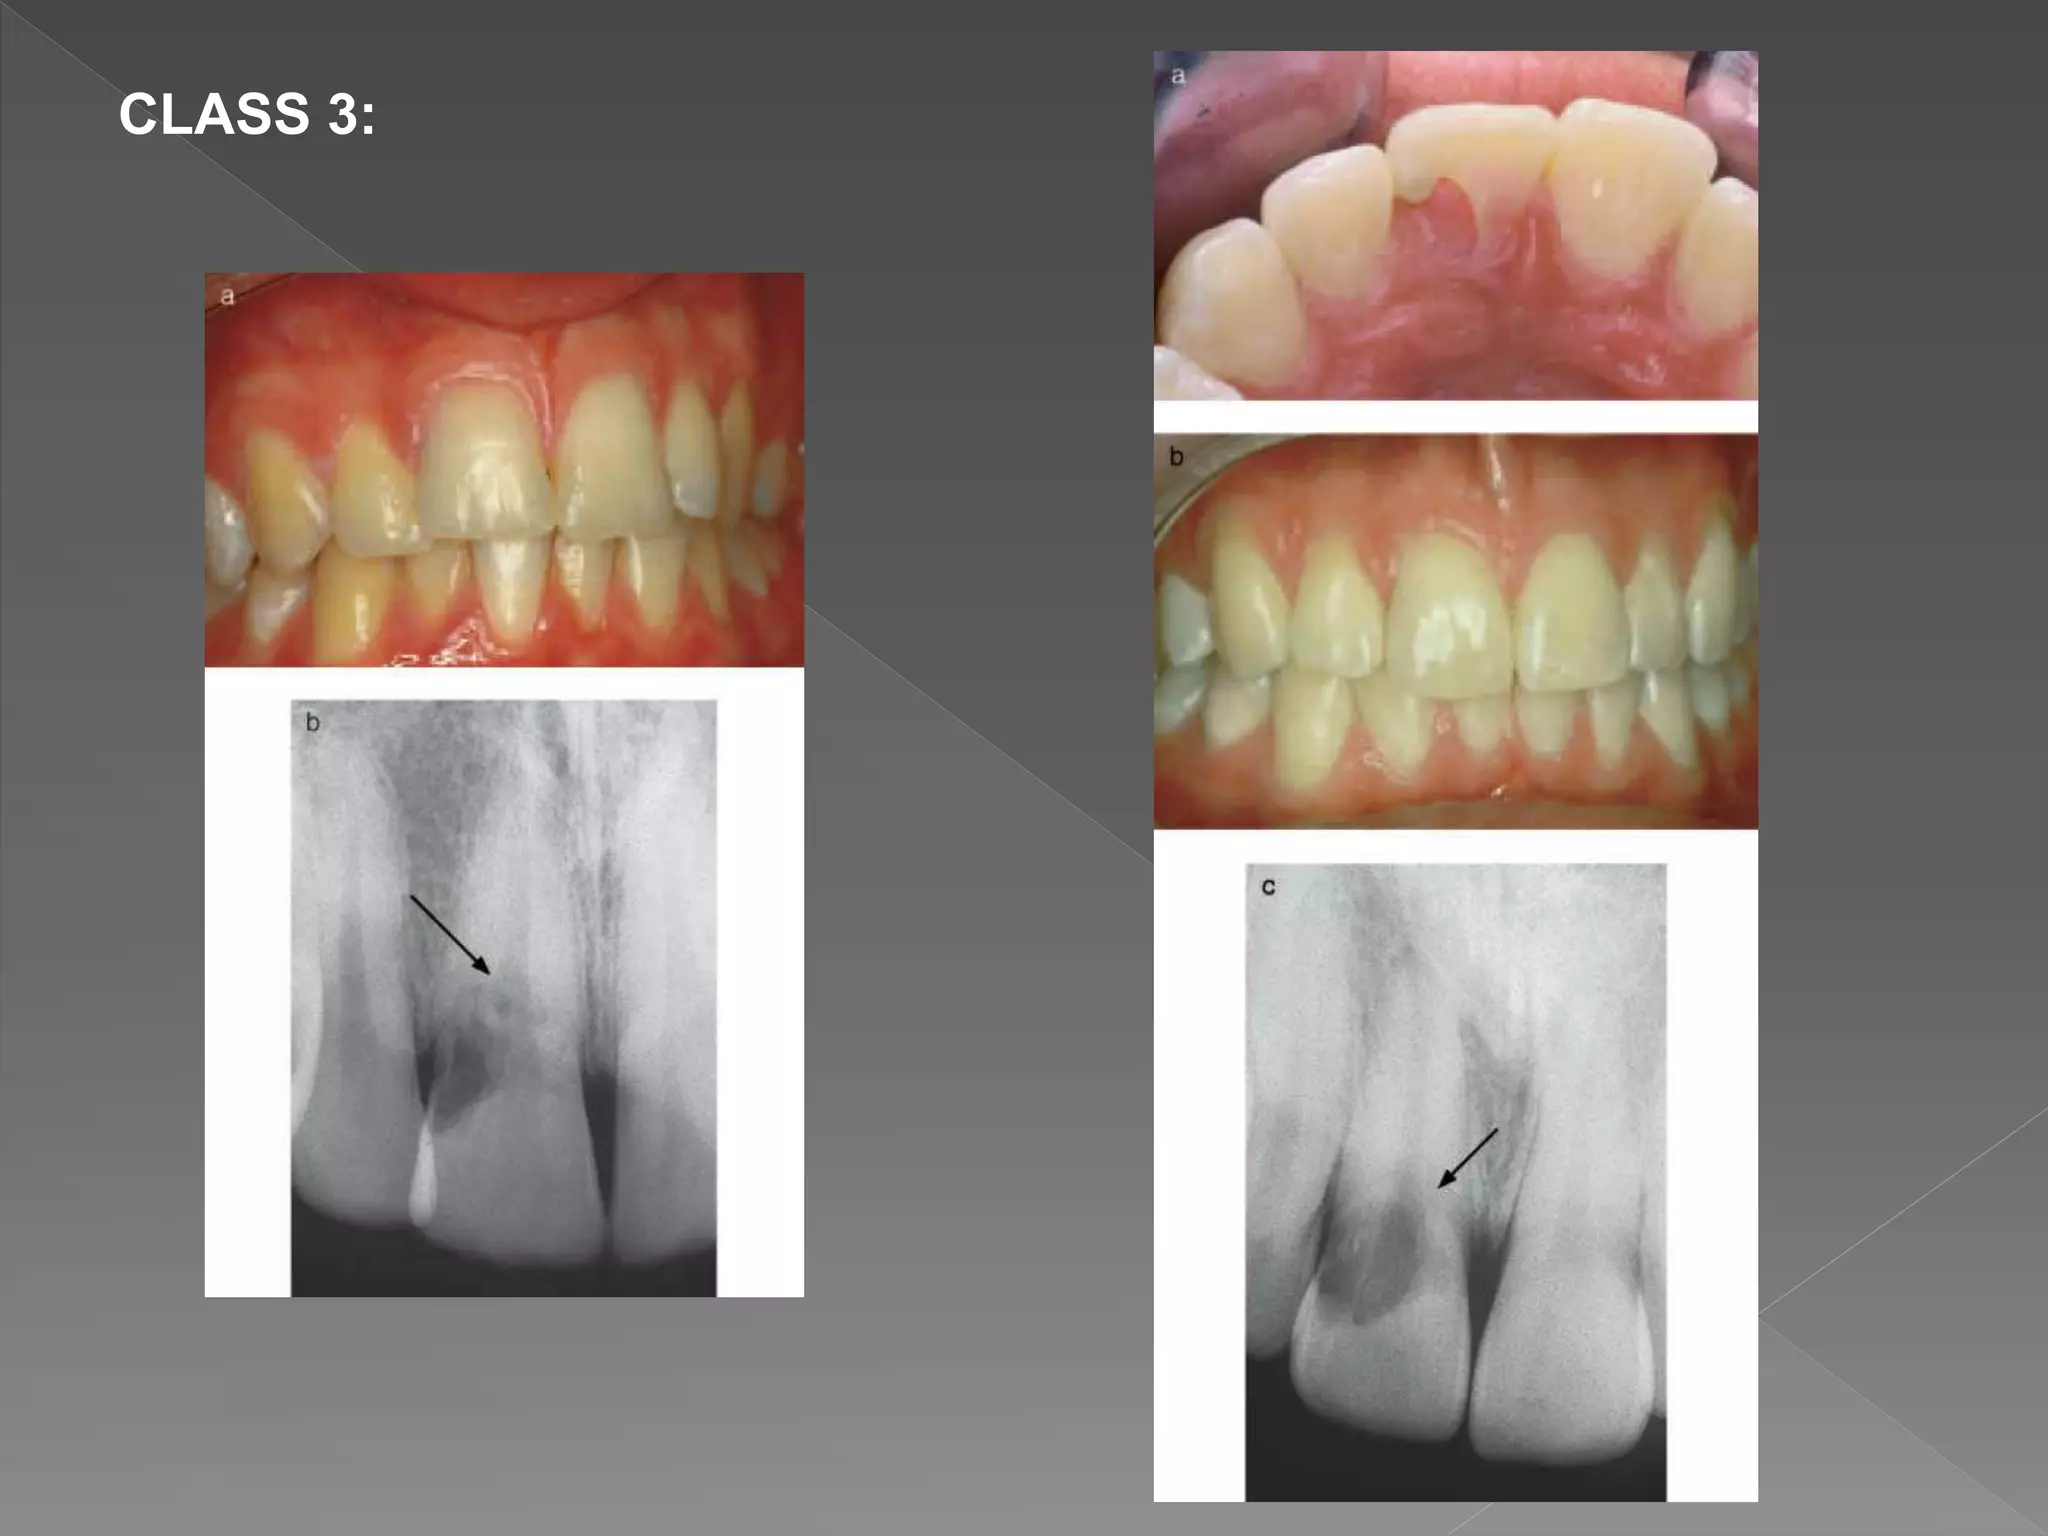

CLASS 3:

 Heithersay concluded that classes 1–3 were treatable, but class

4 lesions were not amenable to treatment, and these cases

would have benefited from alternative treatment such as

extraction and replacement with an implant retained crown

restoration.

 In the instance of classes 1–3, the root canal should be

nonsurgically accessed and temporarily occluded with a finger

spreader or gutta-percha point.

 Then the surgical repair to the resorptive defect might be carried

out without blocking the root canal with filling material.

 Heithersay recommended topical application of a 90%

aqueous solution of trichloroacetic acid, curettage, and

restoration with glass ionomer cement.